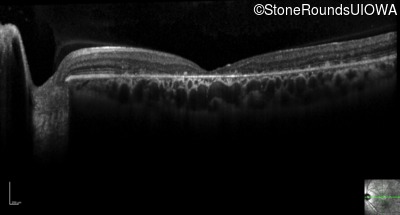

Optical Coherence Tomography - Left - 20/40

Exemplar / OCT Stack

OCT Stack